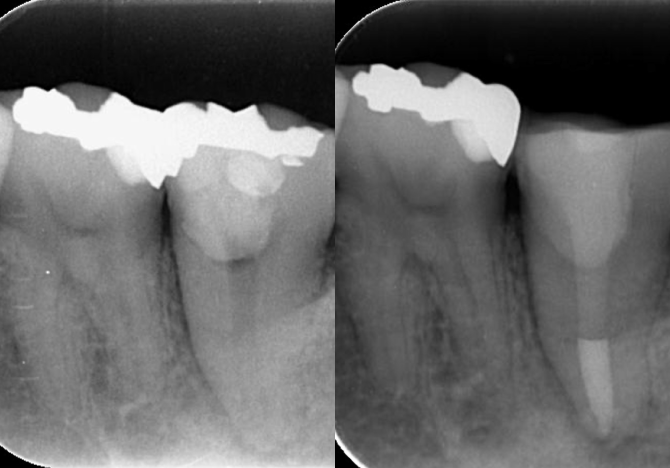

難治性の根管治療で困っている先生がおられましたら、ぜひご紹介ください。根管治療専門医が精密根管治療をいたします。

その際、当院では根管治療のみ治療をします。他の治療や続きの治療は先生の医院でおこなっていただくことをお約束します。